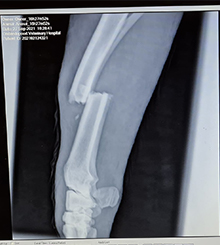

GRACE

Grace's Journey